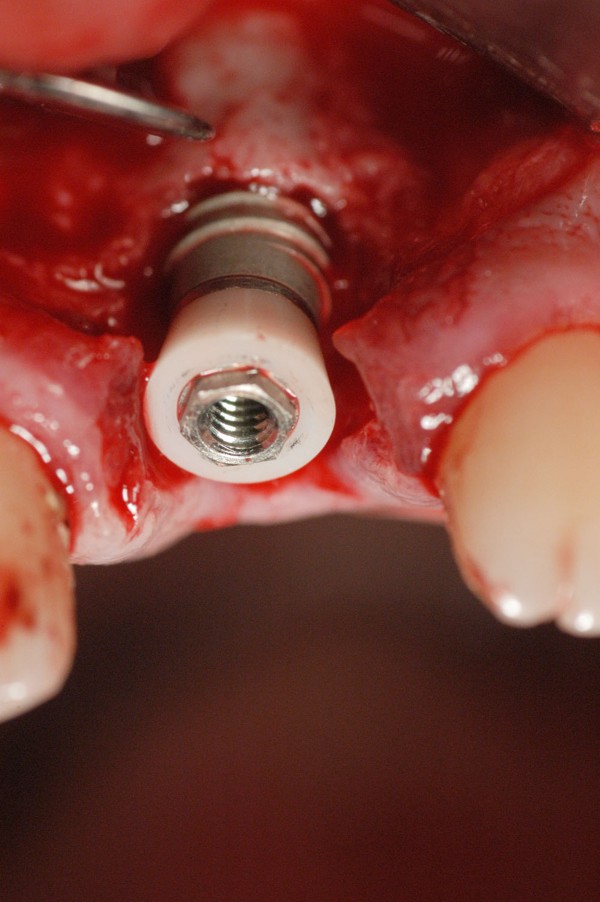

Este artículo pertenece a la categoría: Casos Clínicos

Abstract: Las fuerzas anterógradas traumáticas son en general las causantes de fracturas radiculares en el sector anterior de la boca. Desarrollo: El paciente se presenta a la consulta , con la fractura de una funda de porcelana inyectada en la zona cérvico palatina, solicitando simplemente la reparación en boca para evitar rozamientos linguales. Dicha funda con un perno colado en oro y su correspondiente endodoncia, habían sido realizadas en mi clínica varios años atrás, con un «aparente éxito total». Radiograficamente, se encuentra una fractura radicular cercana al tercio gingival Observada la oclusión de las piezas anteriores, podemos ver que el vínculo ideal de Acoplamiento, no se cumple, habiendo una relación de franco contacto la que ha provocado la fractura. Llevando al paciente a Oclusión en Relación Céntrica, podemos ver el espacio a nivel anterior, correspondiente a la centricidad mandibular. En esa misma posición , es dable percibir una faceta parafuncional mesial del primer premolar superior… …que antagoniza con una faceta parafuncional distal del canino inferior… ..constituyendo un plano inclinado que provoca la antelación mandibular o Discrepancia Horizontal, fracturando la raiz del incisivo central. Extraida la porción coronal de la raiz, pensamos en la realización de un Implante Inmediato, a pesar de la presencia de una fístula dado que se trataba de un central, decisión que obtuvo éxito implantario mas no estético, según veremos luego. Era fundamental conservar lo mas posible las tablas óseas, que de hecho había perdido la porción cervical Realizamos una incisión que conservara las papilas de las piezas adyacentes. Realizamos la exodoncia mediante un instrumento construido «ad hoc» que denomino: Con lo que obtenemos la preservación «ad integrum» de las corticales peridentarias remanentes. Instalamos entonces un implante T.B.R. de 15 mm de largo por 4 mm de diam. con cuello de zirconio de 3,5 mm …quedando tres espiras sin hueso por vestibular, producto de la tabla perdida, Incidimos el periostio a nivel apical del colgajo para obtener mayor paño quirúrgico, y legramos un bolsillo palatino sin incisiones de descarga, para la inserción de la membrana. Suplementamos la carencia ósea vestibular con «BIOSS» …e instalamos una membrana reabsorbible «BIOGUIDE» , que fijamos con el mismo implante, y calzamos por palatino. Suturamos Instalamos nuestra provisional previamente confeccionada, sobre un abuttment de titanio. Y controlamos radiograficamente Pasadas tres semanas del retiro de los puntos, observamos una cicatrización alta que nos muestra el anillo de zirconio del implante. ……………………………………………….. Transcurridos tres meses preparamos una nueva cirugía, dirigida a instalar un injerto autólogo de conectivo en el área del anillo, con un nuevo desplazamiento del colgajo vestibular. Tomamos tejido conectivo del paladar a nivel de los premolares, mediante una incisión mucosa «en libro», y disección del conectivo subyacente. Lo posicionamos en vestibular del anillo de zirconio y lo fijamos mediante sutura Y semanas después nos encontramos con un nuevo fracaso de orden estético. ……………………………………………….. En la actualidad, el caso esta estable , aún con su funda provisional, a la espera de un nuevo intento plástico, mediante Injerto Libre de Encia. ………………………………………………….. ESQUEMA MECÁNICO DEL FENÓMENO …que además de los hechos mostrados en el caso presentado, frecuentemente provocan en el sentido antero posterior los fenómenos de DISPERSIÓN ,en el maxilar superior…y de APIÑAMIENTO en el maxilar inferior. CONCLUSIONES: Además del rigor académico que nos convoca… esta; nuestra casa…nos otorga la confianza que solo da el saber que estamos siempre entre amigos, que cada vez son más. Por tanto es que debo decir: YO fui el responsable de dicha fractura… …porque… …..que hubiera sucedido si hubiera hecho todo el trabajo implantario sin ajustar previamente su oclusión? Seguramente a esta altura del caso…también hubiera fracasado el implante. Siempre decimos que se aprende de los errores más que de los aciertos, y Dr. Carlos A. Acuña Priano

Fig.18(Pie de foto: Instalación de Implante)

Fig .19(Pie de foto: espiras al descubierto)